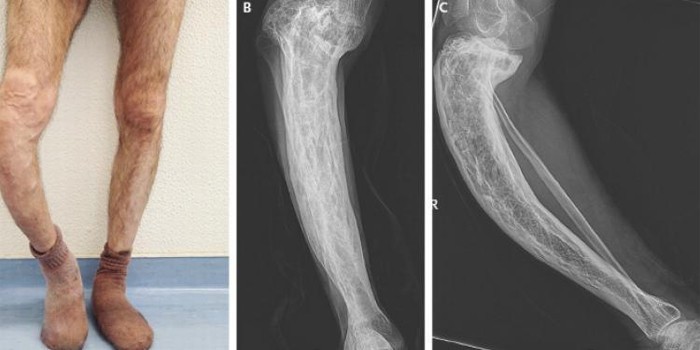

На ранній стадії розвитку симптоми захворювання проявляються частими переломами. У міру прогресування процесу виникають ниючі болі, які, на відміну від остеоартриту, посилюються у стані спокою. На пізній стадії деформація скелета визначається за фото:

- при пошкодженні хребта утворюється виражений кіфоз (викривлення, сутулість);

- якщо постраждали кістки тазу, коротшає тулуб;

- коли в процес залучені нижні кінцівки, порушується рухливість суглобів, з'являються Х або О-подібні викривлення ніг.

Найінформативнішим методом діагностики захворювання вважається рентгенологічне дослідження.

На знімку виявляються такі симптоми хвороби:

При ураженні хребта, ребер та кінцівок:

- потовщення та деформація кісток;

- ущільнення кісткової системи;

- клиноподібна форма хребців;

- осередки остеопорозу.